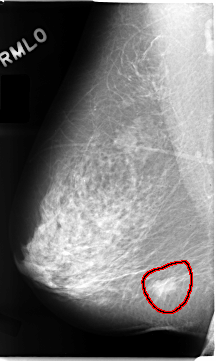

C_0102_1.RIGHT_MLO

RIGHT_MLO LINES 4688 PIXELS_PER_LINE 2800 BITS_PER_PIXEL 12 RESOLUTION 50 OVERLAY

FILE: C_0102_1.RIGHT_MLO.OVERLAY

TOTAL_ABNORMALITIES 1

ABNORMALITY 1

LESION_TYPE MASS SHAPE IRREGULAR MARGINS SPICULATED

ASSESSMENT 5

SUBTLETY 5

PATHOLOGY MALIGNANT

TOTAL_OUTLINES 1

BOUNDARY